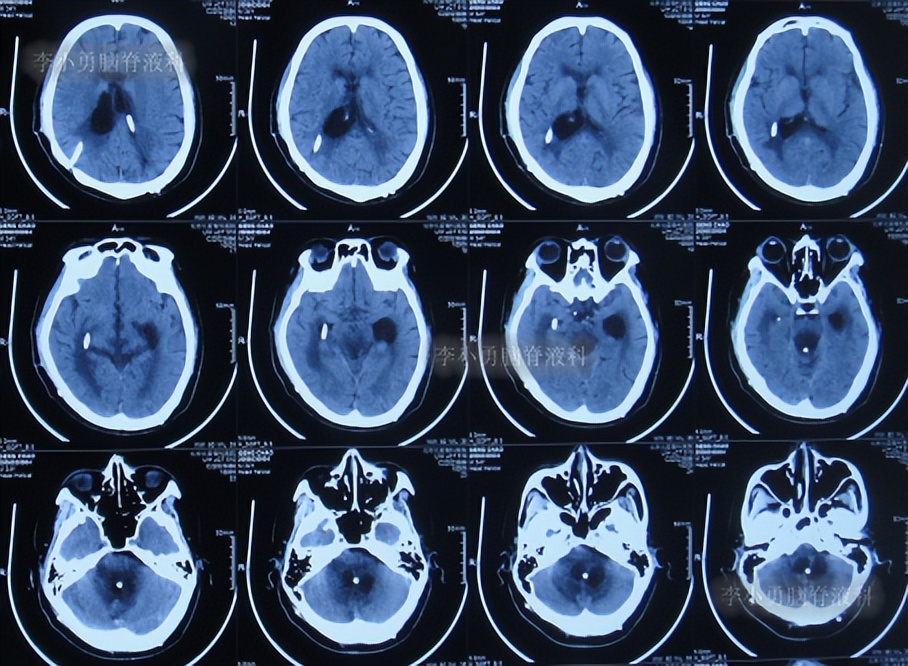

2022年10月25日(入院治疗130天),肺部 CT示感染有好转(图-58);常规检查头颅CT示脑室引流术后状态,未见异常(图-59),考虑夹闭侧脑室和颞角引流管。

图-58:2022年10月25日头颅CT

图-59:2022年10月25日肺部 CT

夹闭引流管后10天左右,脑室未扩张,于是拔除了侧脑室和颞角的引流管,进行了脑室腹腔分流术。

2022年11月15日(李小勇脑脊液科治疗151天)出院,出院时:意识正常,言语交流基本正常,自己走路差点(图-60);头颅CT示未见异常(图-61)。

图-60:2022年11月15日

图-61:出院时头颅CT